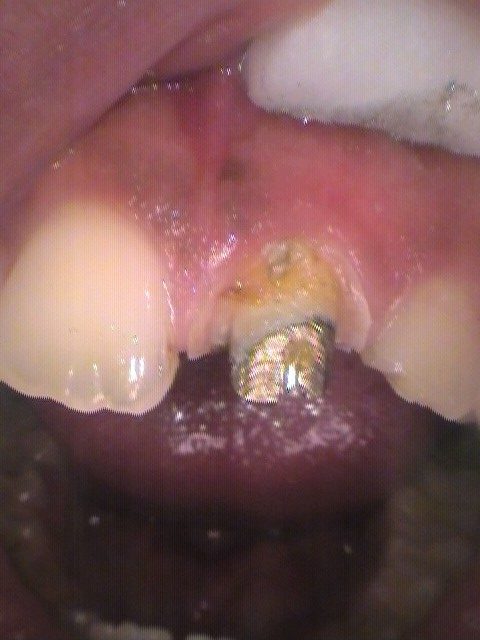

まずはかぶせ物を削って外します。

外すと、中に金属が見えます。

これはメタルコアという金属の土台で、いわゆる差し歯のさしてある部分です。